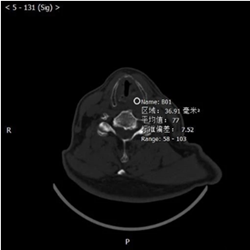

影像图片

评论: 声门上层面喉左后壁增厚,呈软组织密度肿块影,边界不清,左侧杓状软骨大部分显示不清,左侧甲状软骨边缘毛糙,增强扫描呈渐进性轻度强化。